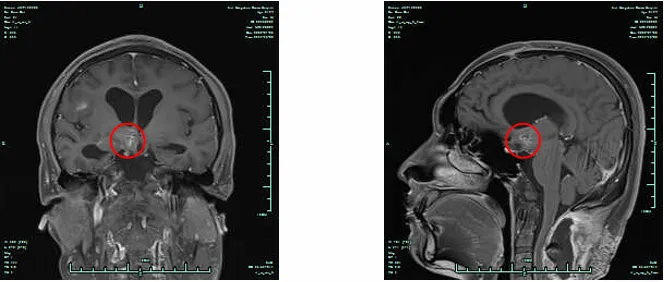

图1. 放疗前头颅MRI检查结果(2022.7.20)

图2.放疗前脊髓MRI检查结果(2022.7.22)